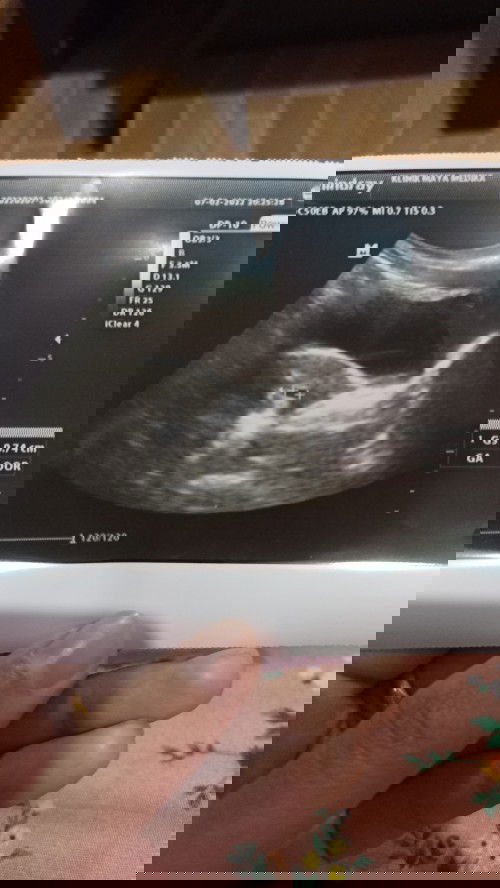

10 week blum terlihat janin

Hai bun, sya kmrn periksa usg k bubidan klo sesuai hpht hrusnya sdh 10 week, tapi kmrn klo sesuai ukuran kantong 7 week, dan dedenya blm terlihat masih kantung, wajar ga ya bun? #seriusnanya #bantusharing #ingintahu #pleasehelp #firstbaby #1stimemom

Bunda disini adakah yg usg di usia 7w masih terlihat kantung saja, dede janinnya blm terlihat?

Bunda disini adakah yg usg di usia 7w masih terlihat kantung saja, dede janinnya blm terlihat? Wajarkah? Saya worry karena di bilang dokter takut BO.. #seriusnanya #bantusharing #firstbaby

Bunda adakah yg di usia 7 week masih terlihat kantong janin saja?

Bunda adakah yg di usia 7 week masih terlihat kantong janin saja? #seriusnanya #bantusharing #ingintahu #pleasehelp #firstbaby